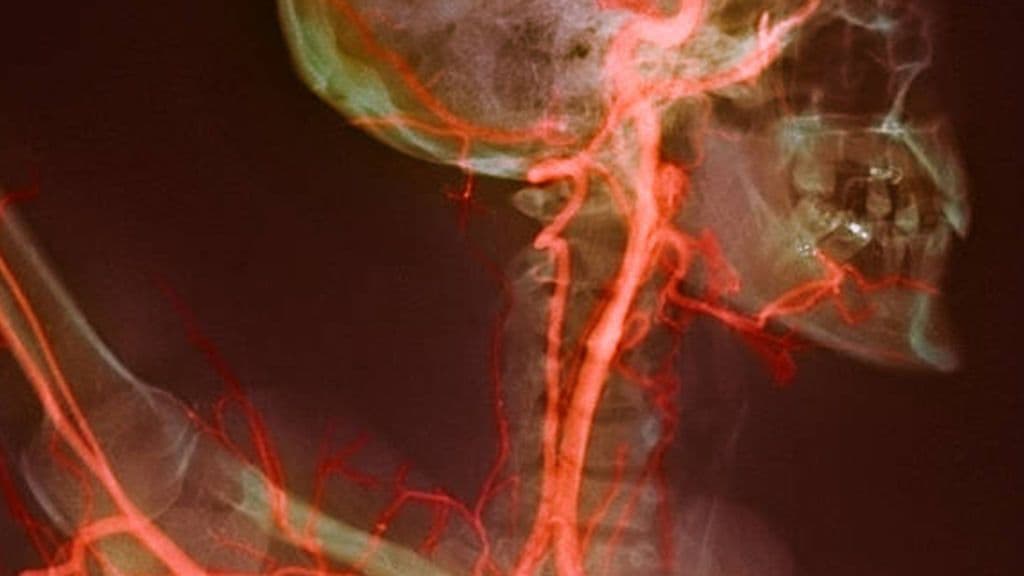

تضيق الشريان السباتي: الأسباب والأعراض والتشخيص والعلاج